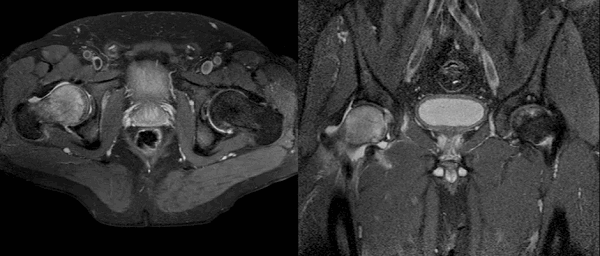

Представлена первая из девяти аксиальных Т1 -взвешенных МР-томограмм левого тазобедренного сустава. Запирательный нерв лежит поверх внутренней запирательной мышцы. Седалищный нерв покидает таз через большую седалищную вырезку. Сухожилие поясничной мышцы визуализируется в виде отчетливой структуры с сигналом низкой интенсивности у заднего края подвздошно-поясничной мышцы. У места своего начала от передней нижней подвздошной ости визуализируется передняя головка прямой мышцы бедра. Визуализируются сухожилия обеих головок прямой мышцы бедра. Подвздошно-поясничная мышца лежит медиальнее прямой мышцы бедра, а портняжная мышца пересекает ее по диагонали. Седалищный нерв после выхода из таза идет косо и на аксиальных срезах имеет овальную форму. На этой томограмме визуализируется слияние передней и задней головок прямой мышцы бедра. Медиальные сосуды, огибающие бедренную кость, оборачиваются вокруг заднего края большого вертела и кровоснабжают проксимальный отдел бедренной кости. Визуализируется внутренняя запирательная мышца, идущая от медиальной поверхности вертлужной впадины, огибающая под острым углом седалищную кость и проходящая в передне-наружном направлении к месту своего прикрепления в грушевидной ямке. Сухожилия малой и средней ягодичных мышц достигают места своего прикрепления к большому вертелу. Сухожилие поясничной мышцы представляет собой отчетливую структуру у заднемедиального края подвздошно-поясничной мышцы. Сухожилие полуперепончатой мышцы начинается кпереди от общего сухожилия полусухожильной и двуглавой мышц бедра. Лучше всего, по-видимому, рассматривать большую приводящую мышцу как две отдельные мышцы. Показанная здесь верхняя порция имеет близкую к горизонтальной направленность, иногда называется малой приводящей мышцей и приводит бедро. Более вертикально направленная порция визуализируется здесь начинающейся от седалищного бугра. Она имеет многочисленные точки прикрепления к диафизу бедренной кости и небольшую вертикально ориентированную порцию, прикрепляющуюся к приводящему бугорку медиального мыщелка бедренной кости. Первая из трех отобранных косых аксиальных МР-томограмм правого тазобедренного сустава в режиме Т1. Косая аксиальная плоскость наклонена вдоль оси шейки бедренной кости и может использоваться при определении признаков бедренно-вертлужного импиджмента. Косая проекция также полезна при оценке мышц. Круговая зона представляет собой утолщение и относительное сужение капсулы сустава. Капсула прикрепляется у основания шейки бедренной кости по межвертельной линии. Капсула сустава усилена подвздошно-бедренной, лонно-бедренной и седалищно-бедренной связками. Этот срез получен через нижний край ямки головки бедренной кости. Передняя и задняя части вертлужной губы визуализируются в виде треугольников с сигналом низкой интенсивности, которые углубляют вертлужную впадину.